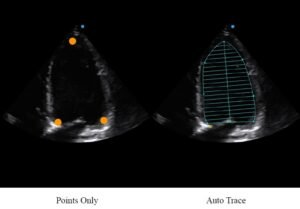

Automatyczne EF

Ocena funkcji serca wymaga dokładności i szybkości, ponieważ konieczne jest wykonanie

różnych obliczeń. Automatyczne śledzenie i obliczanie oznacza większą wydajność w praktyce.

Funkcja Auto EF, oparta na technologii śledzenia plamek, umożliwia pozyskiwanie 2D EF i

objętości w ramach usprawnionego przepływu pracy.